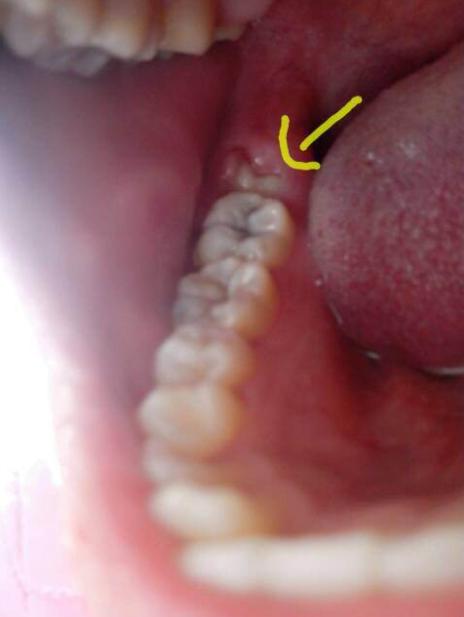

牙医经常在临床评估过程中诊断冠周炎。 牙医将通过检查智齿并检查体征和冠周炎的外观来诊断病情。

牙医将检查牙龈是否发炎,发红,肿胀或流脓。 他们还将寻找患处是否有口香糖瓣。

牙医还可能需要进行X射线检查,以检查智齿的排列并排除引起疼痛的其他可能原因,例如蛀牙。